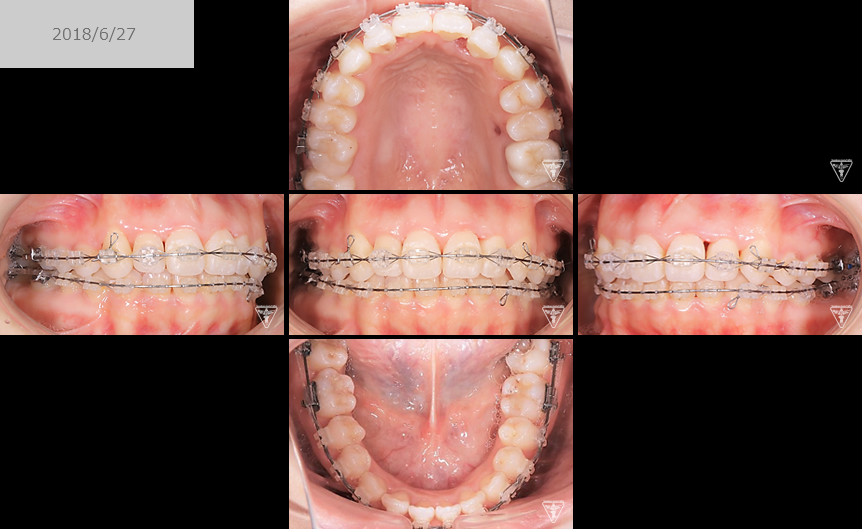

矯正器具 装着時の治療過程